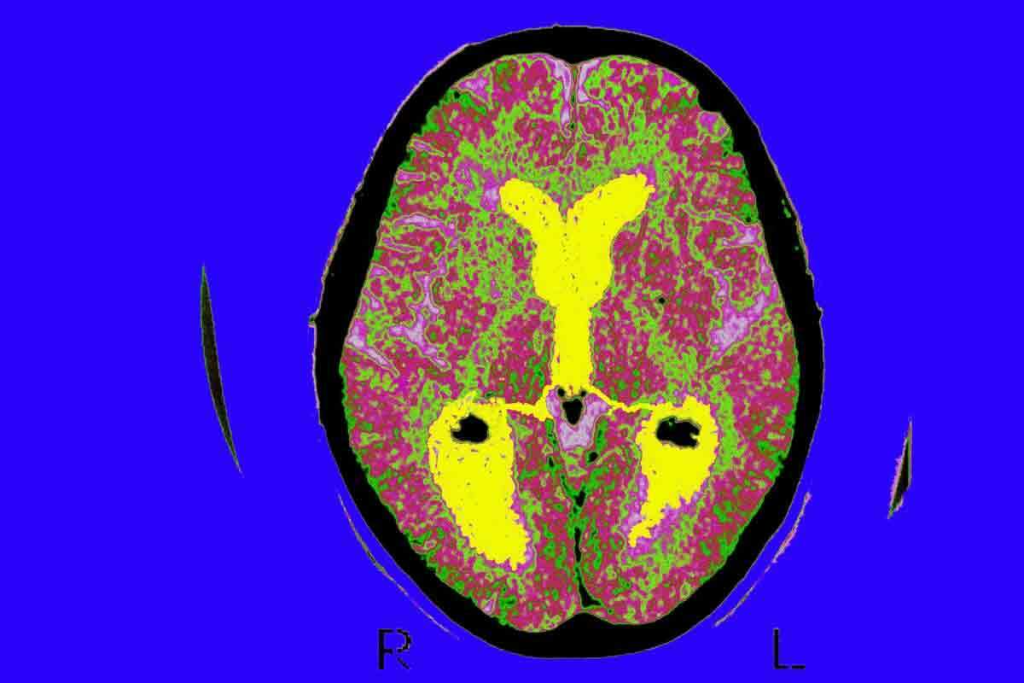

Diagnosing brain tumors needs precise imaging to find the best treatment. At Liv Hospital, we use top-notch imaging tech for accurate diagnoses. For brain tumor detection, CT scans and MRI are both useful. But MRI is better because it’s more sensitive to soft tissue issues.

The Tisch Brain Tumor Center says MRI is the best for brain tumor imaging. It finds 60% of tumors, while CT scans find 50%. MRI is great for seeing soft tissues, blood vessels, and tumors, making it the top choice for finding brain tumors.

Diagnostic Capabilities for Brain Tumor Detection

Detection Rates: Statistical Comparison

Research shows MRI finds brain tumors in about 60% of cases. CT scans find them in about 50%. This is a big difference, mainly for small or deep tumors. MRI’s better soft tissue contrast helps it spot some tumors better.

Here’s a comparison of detection rates:

| Imaging Modality | Detection Rate |

| MRI | 60% |

| CT Scan | 50% |

Types of Brain Tumors Better Visualized by MRI

MRI’s detailed soft tissue images are a big plus. It’s best for spotting small or complex tumors. Tumors near the brainstem or optic nerves are clearer on MRI.

Soft Tissue Contrast: Why It Matters for Tumor Identification

Soft tissue contrast is key for spotting and understanding brain tumors. It helps doctors tell different soft tissues apart in the brain. This is vital for treating brain tumors rigcorrectlyRI’s Superior Soft Tissue Resolution

Magnetic Resonance Imaging (MRI) beats Computed Tomography (CT) scans in showing soft tissues. MRI can spot tiny differences in soft tissues. This makes MRI a top choice for brain tumor care.

We use MRI to get clear pictures of brain tumors. This helps us make accurate diagnoses and plans. MRIs’ sharp images let us see how far tumors spread and where they are in relation to other parts of the brain.